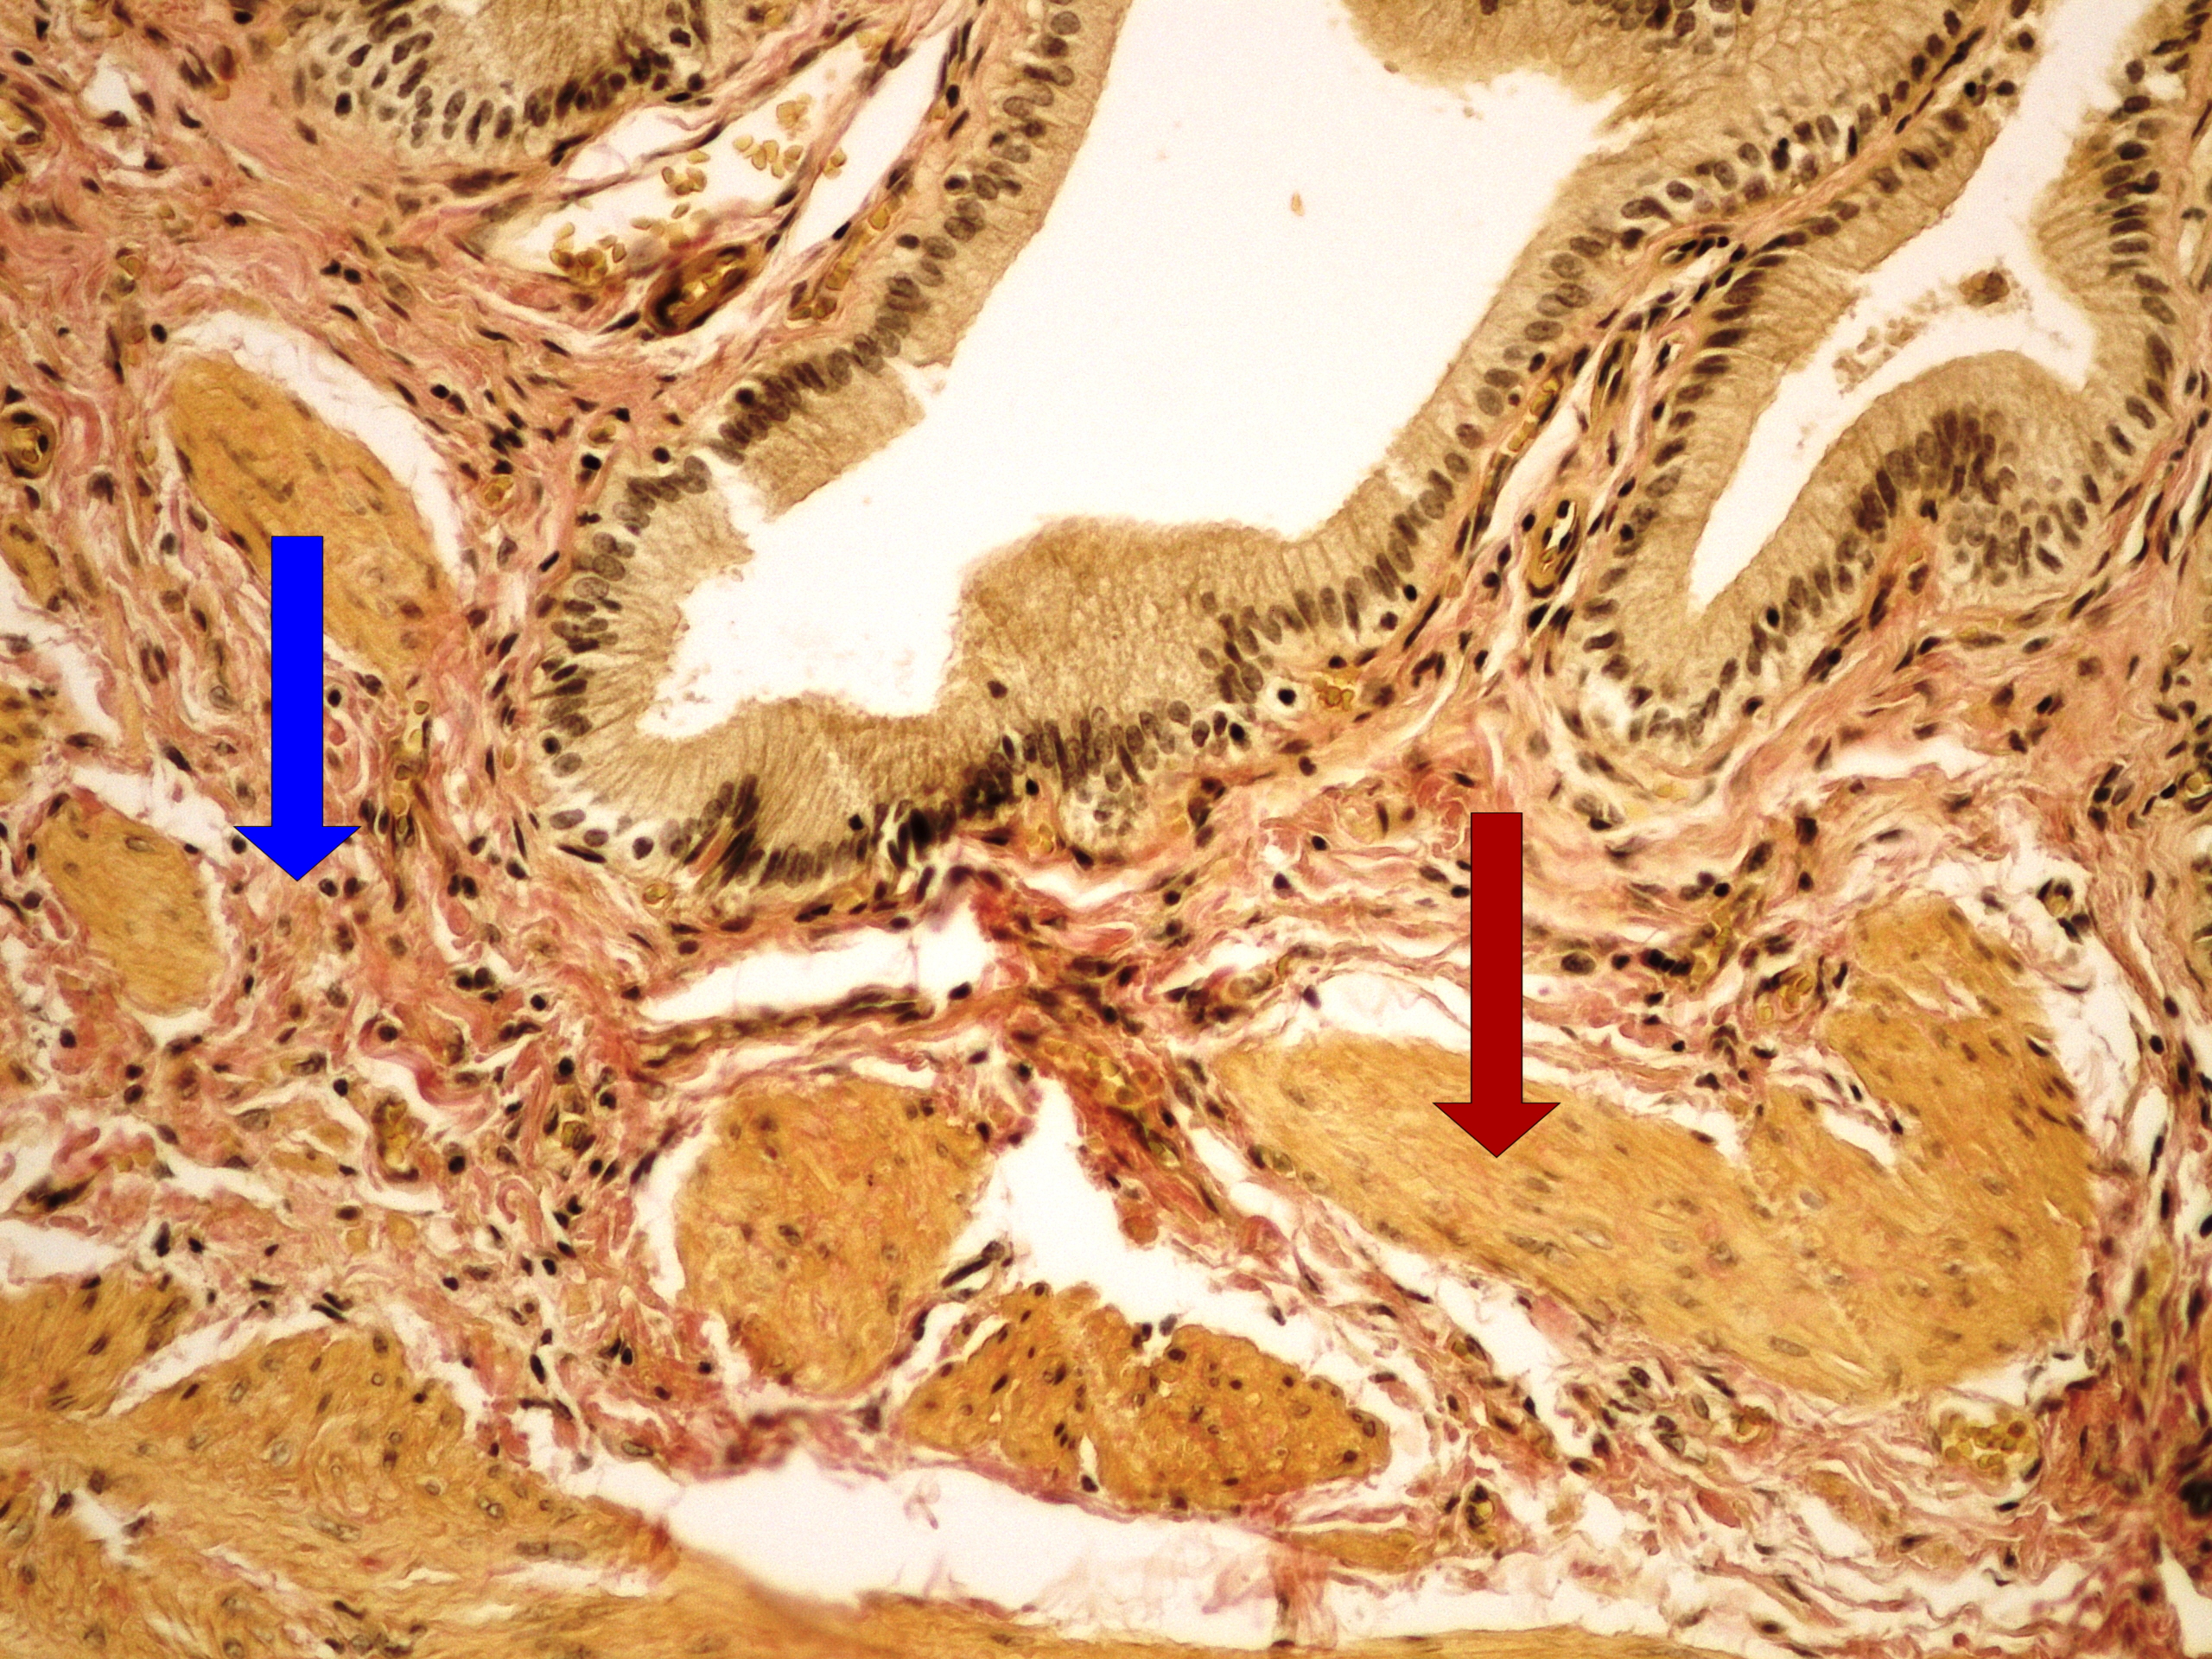

Карнификация Легкого: Микропрепараты и Диагностика

Раздел: Калейдоскоп образов